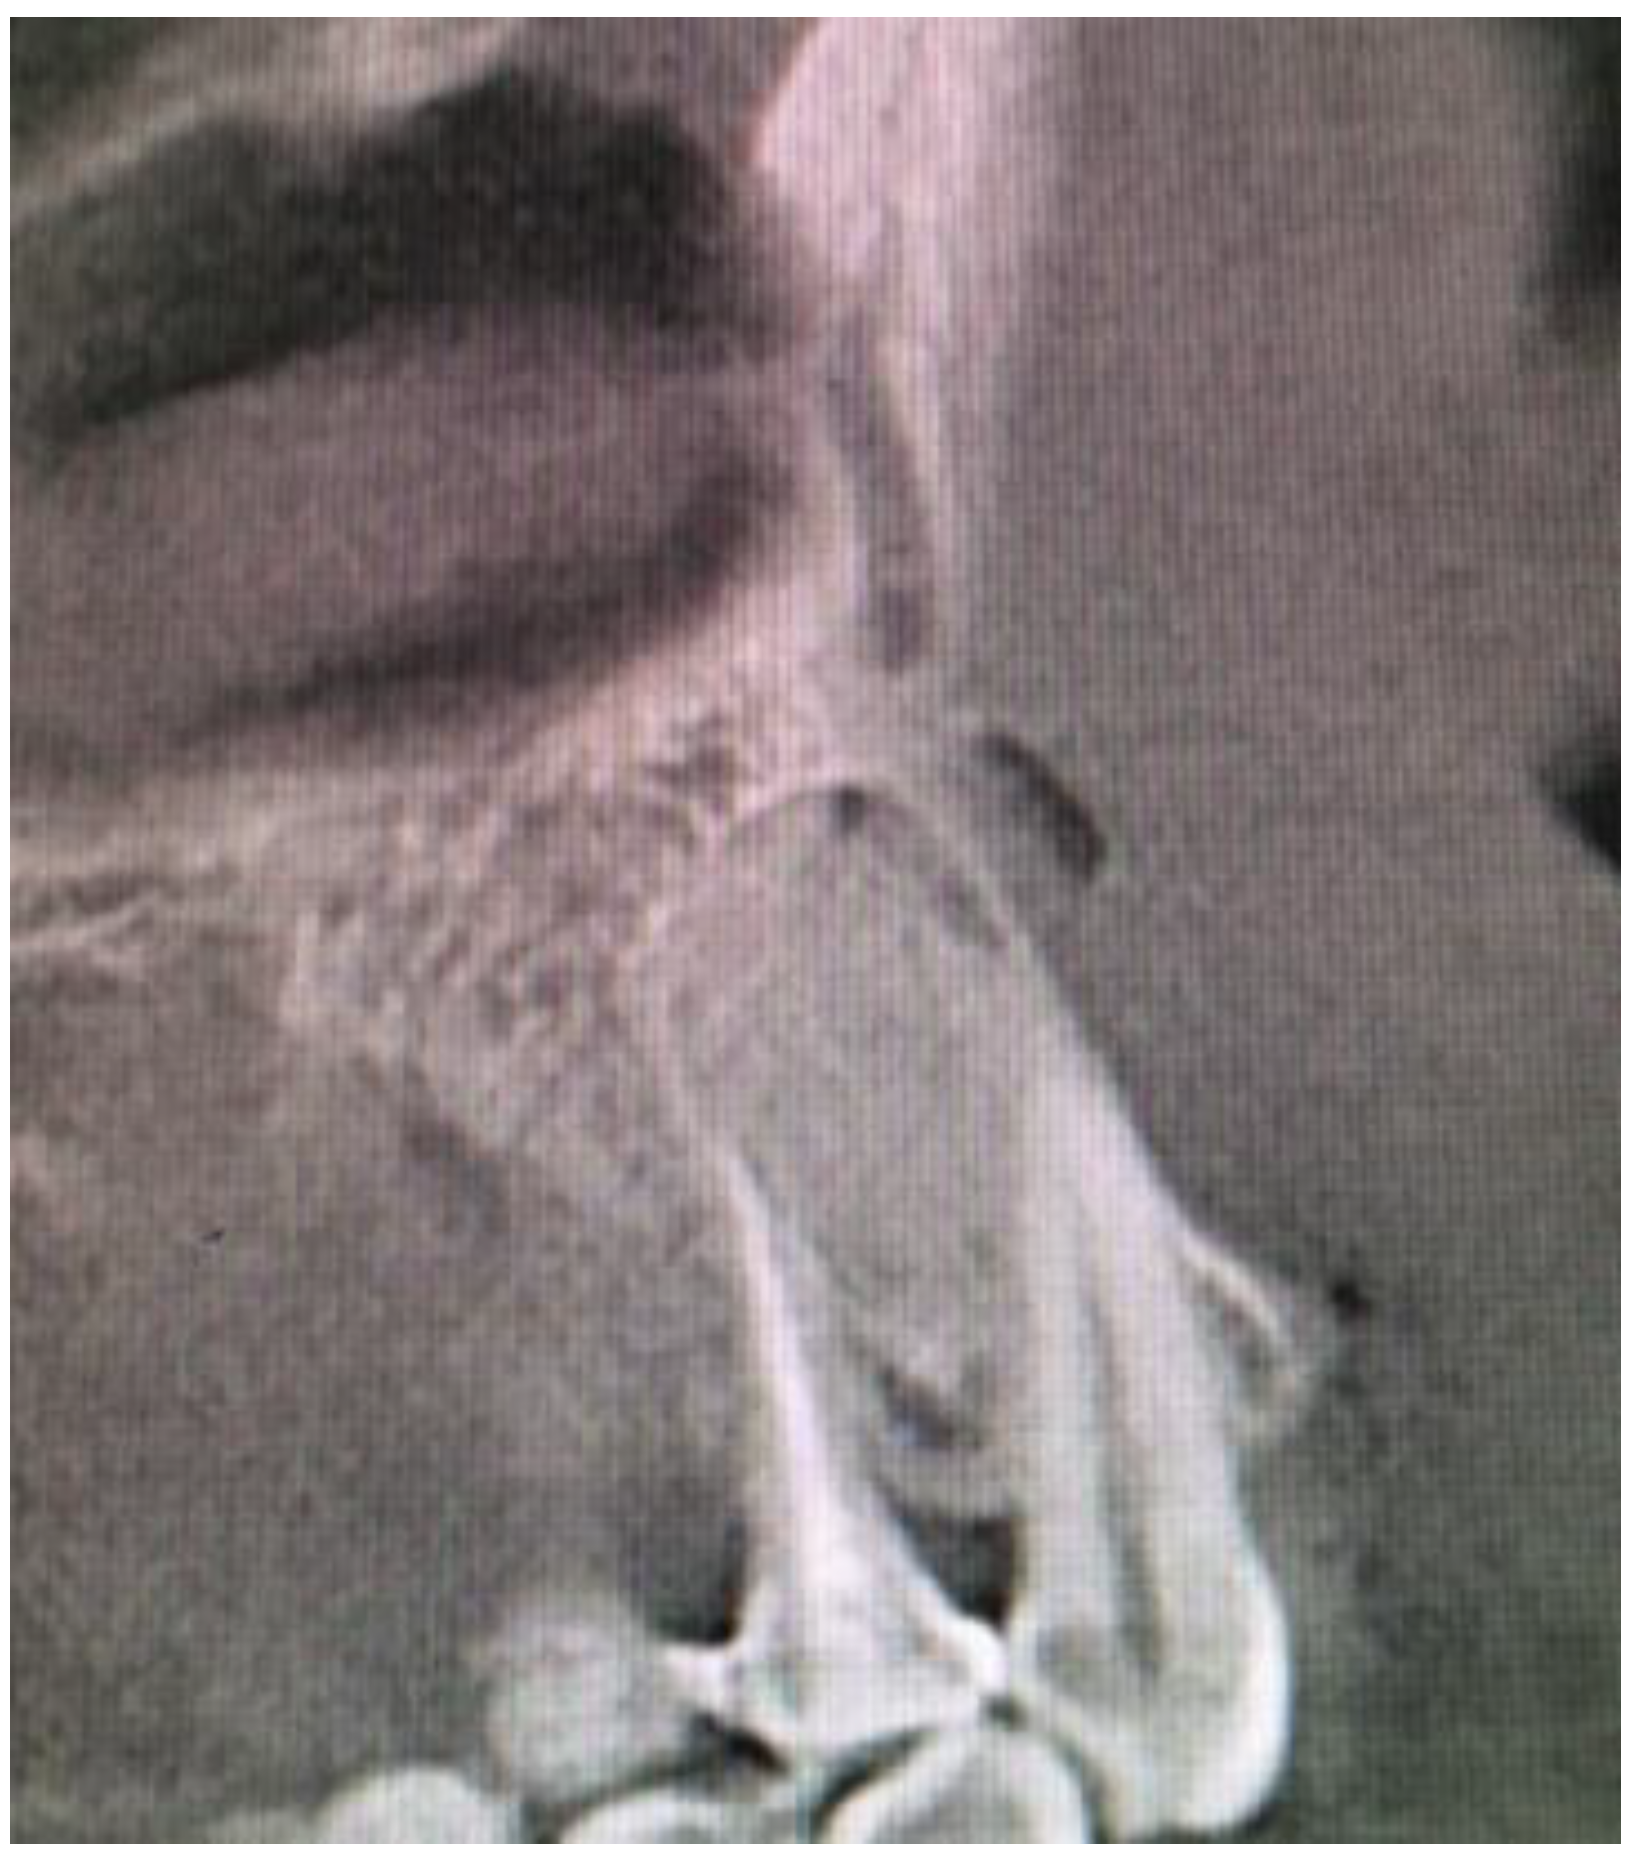

A 35-year-old female patient presented with a small, well-defined lesion on the attached gingival area, approximately 5/6 mm in diameter between roots of teeth 23–24, reported to the Privat Dental Clinic. The patient’s main concern was focused on gingival asymmetry and a tumor-like mass, painless and sometimes tender on tooth brushing. Clinical anamnesis revealed the occurrence of this asymptomatic mass for over 6 months. Because of swelling and atypical cortical expansion, the patient was referred for consultation and treatment. The patient was generally healthy without any chronic illness or important medical and dental past. A routine panoramic radiograph revealed a well-defined, radiolucent, left maxillary lesion located between the roots of the canine and first maxillary premolar (Figure 1 and Figure 2).

Figure 1. Panoramic radiograph slice from CBCT evaluation of LPC.